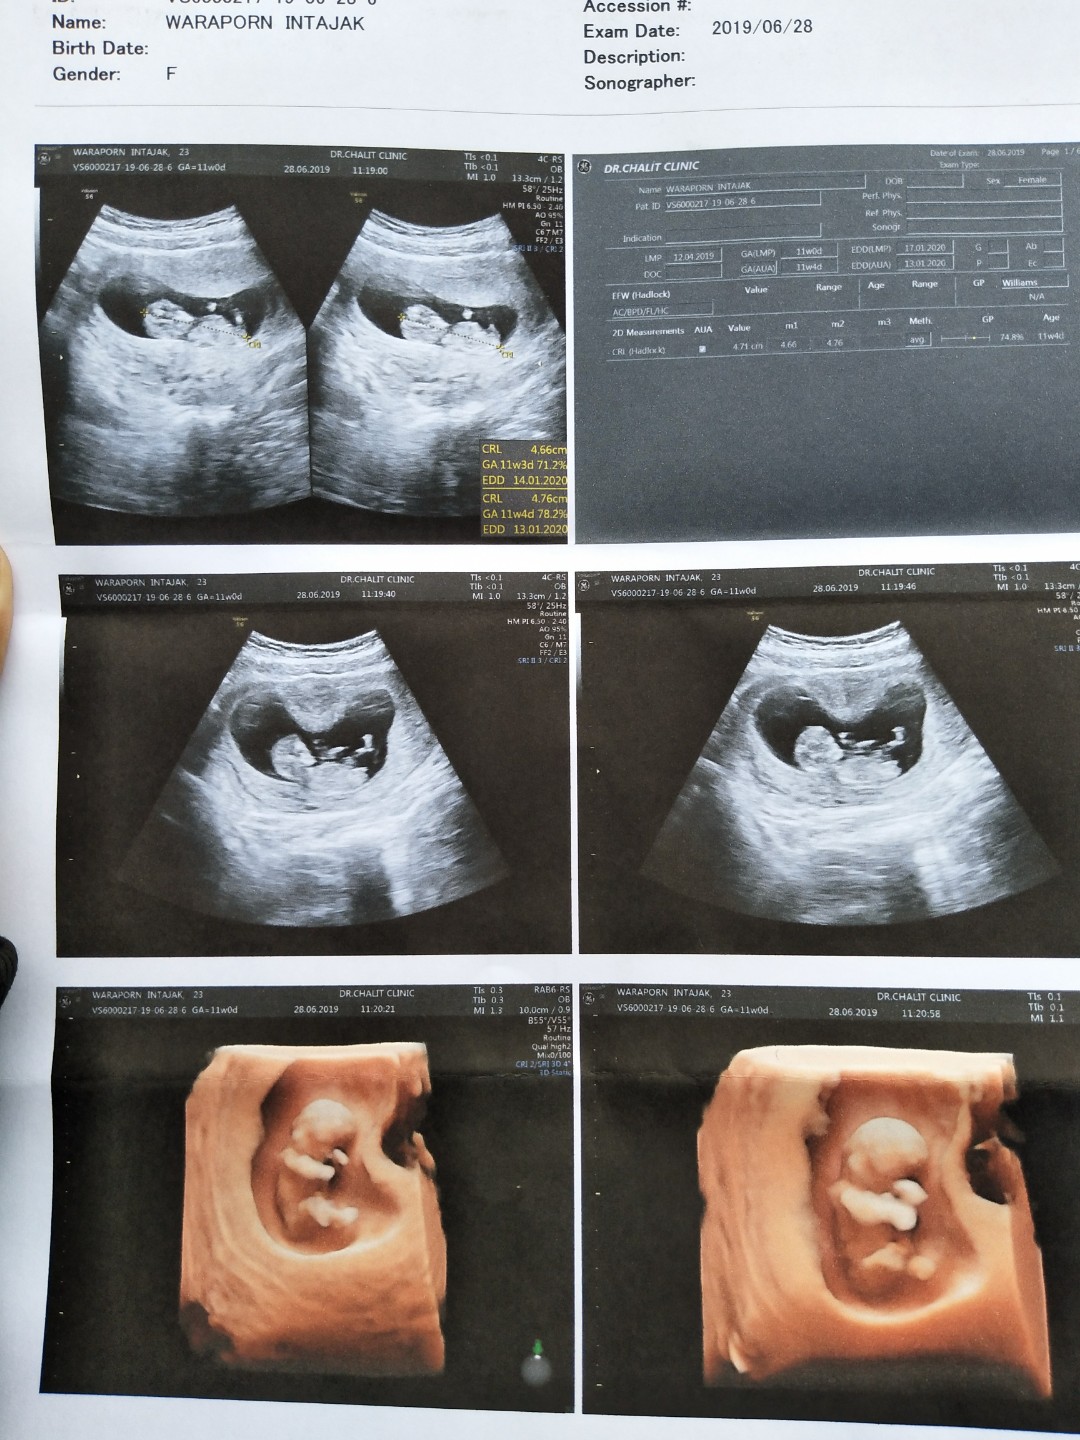

11w จ้า

13 week ค่ะ